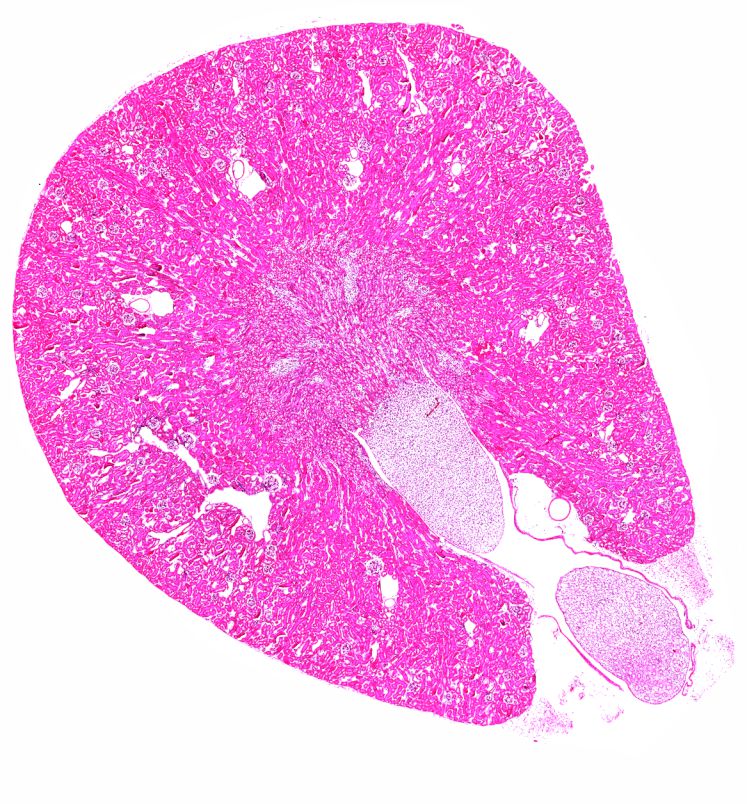

Plasmalemma vesicle-associated protein 1 (PLVAP) ist ein zentrales Strukturprotein, das für die Bildung sogenannter fenestraler Diaphragmen unerlässlich ist – feiner Membranstrukturen, die in bestimmten Kapillaren vorkommen und dort die Durchlässigkeit der Gefäßwand regulieren. Solche spezialisierten Gefäße finden sich unter anderem in der Niere, im Auge und im Pankreas, wo sie eine entscheidende Rolle beim selektiven Austausch von Molekülen zwischen Blut und Gewebe spielen.

In diesem Projekt wird untersucht, welche Auswirkungen der gezielte Verlust dieser Diaphragmen – herbeigeführt durch einen induzierten PLVAP-Mangel – auf die Gewebeintegrität verschiedener Organe sowie auf die Zusammensetzung des Blutes bei adulten Mäusen hat. Ein besonderer Fokus liegt dabei auf der Choriokapillaris des Auges, um die Rolle der choriokapillaren Diaphragmen für die Aufrechterhaltung des retinalen Pigmentepithels (RPE) und der Photorezeptoren zu untersuchen.

Für Biologiestudierende bietet das Projekt – im Rahmen eines sechswöchigen Masterpraktikums oder einer Abschlussarbeit – einen spannenden und vielfältigen Einblick in aktuelle biomedizinische Forschung. Es umfasst ein breites Methodenspektrum, darunter Techniken der Molekularbiologie wie quantitative RT-PCRs und Western Blot Analysen, immunhistochemische und histologische Färbungen an Paraffin-/Kryo-Schnitten und Flachpräparaten, sowie hochauflösende Elektronenmikroskopie. Besonders reizvoll ist die organübergreifende Herangehensweise: Neben dem Auge werden auch Pankreas, Niere, Leber, Speichel- und Tränendrüsen untersucht. Ergänzt wird dies durch Blutanalysen. Durch diese Vielfalt bietet das Projekt die Möglichkeit, eine breite Palette experimenteller Methoden kennenzulernen und gleichzeitig ein tieferes Verständnis für systemische Zusammenhänge zwischen unterschiedlichen Organen zu entwickeln.